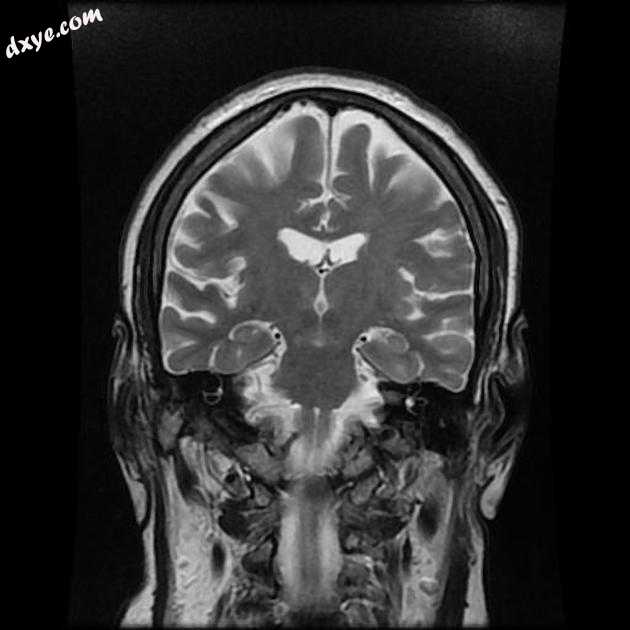

Coronal T2

MRI 序列显示左侧大脑中动脉 (MCA) 区域分布中的弥散受限区域,在 FLAIR 序列上不可见。在 GE 序列上没有看到出血性转化。 MRA 3D-TOF 显示左侧大脑中动脉完全闭塞。

早期超急性大脑中动脉 (MCA) 区域梗死的 MRI 特征。